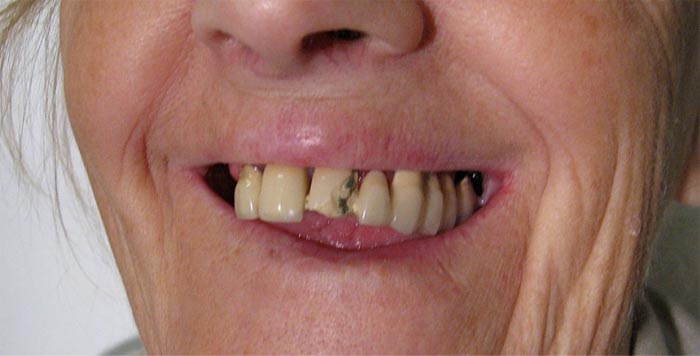

Fall Nr. 2: Vorläufiger herausnehmbarer Zahnersatz zum Wiedererlangen der Mundästhetik in drei bis fünf Tagen